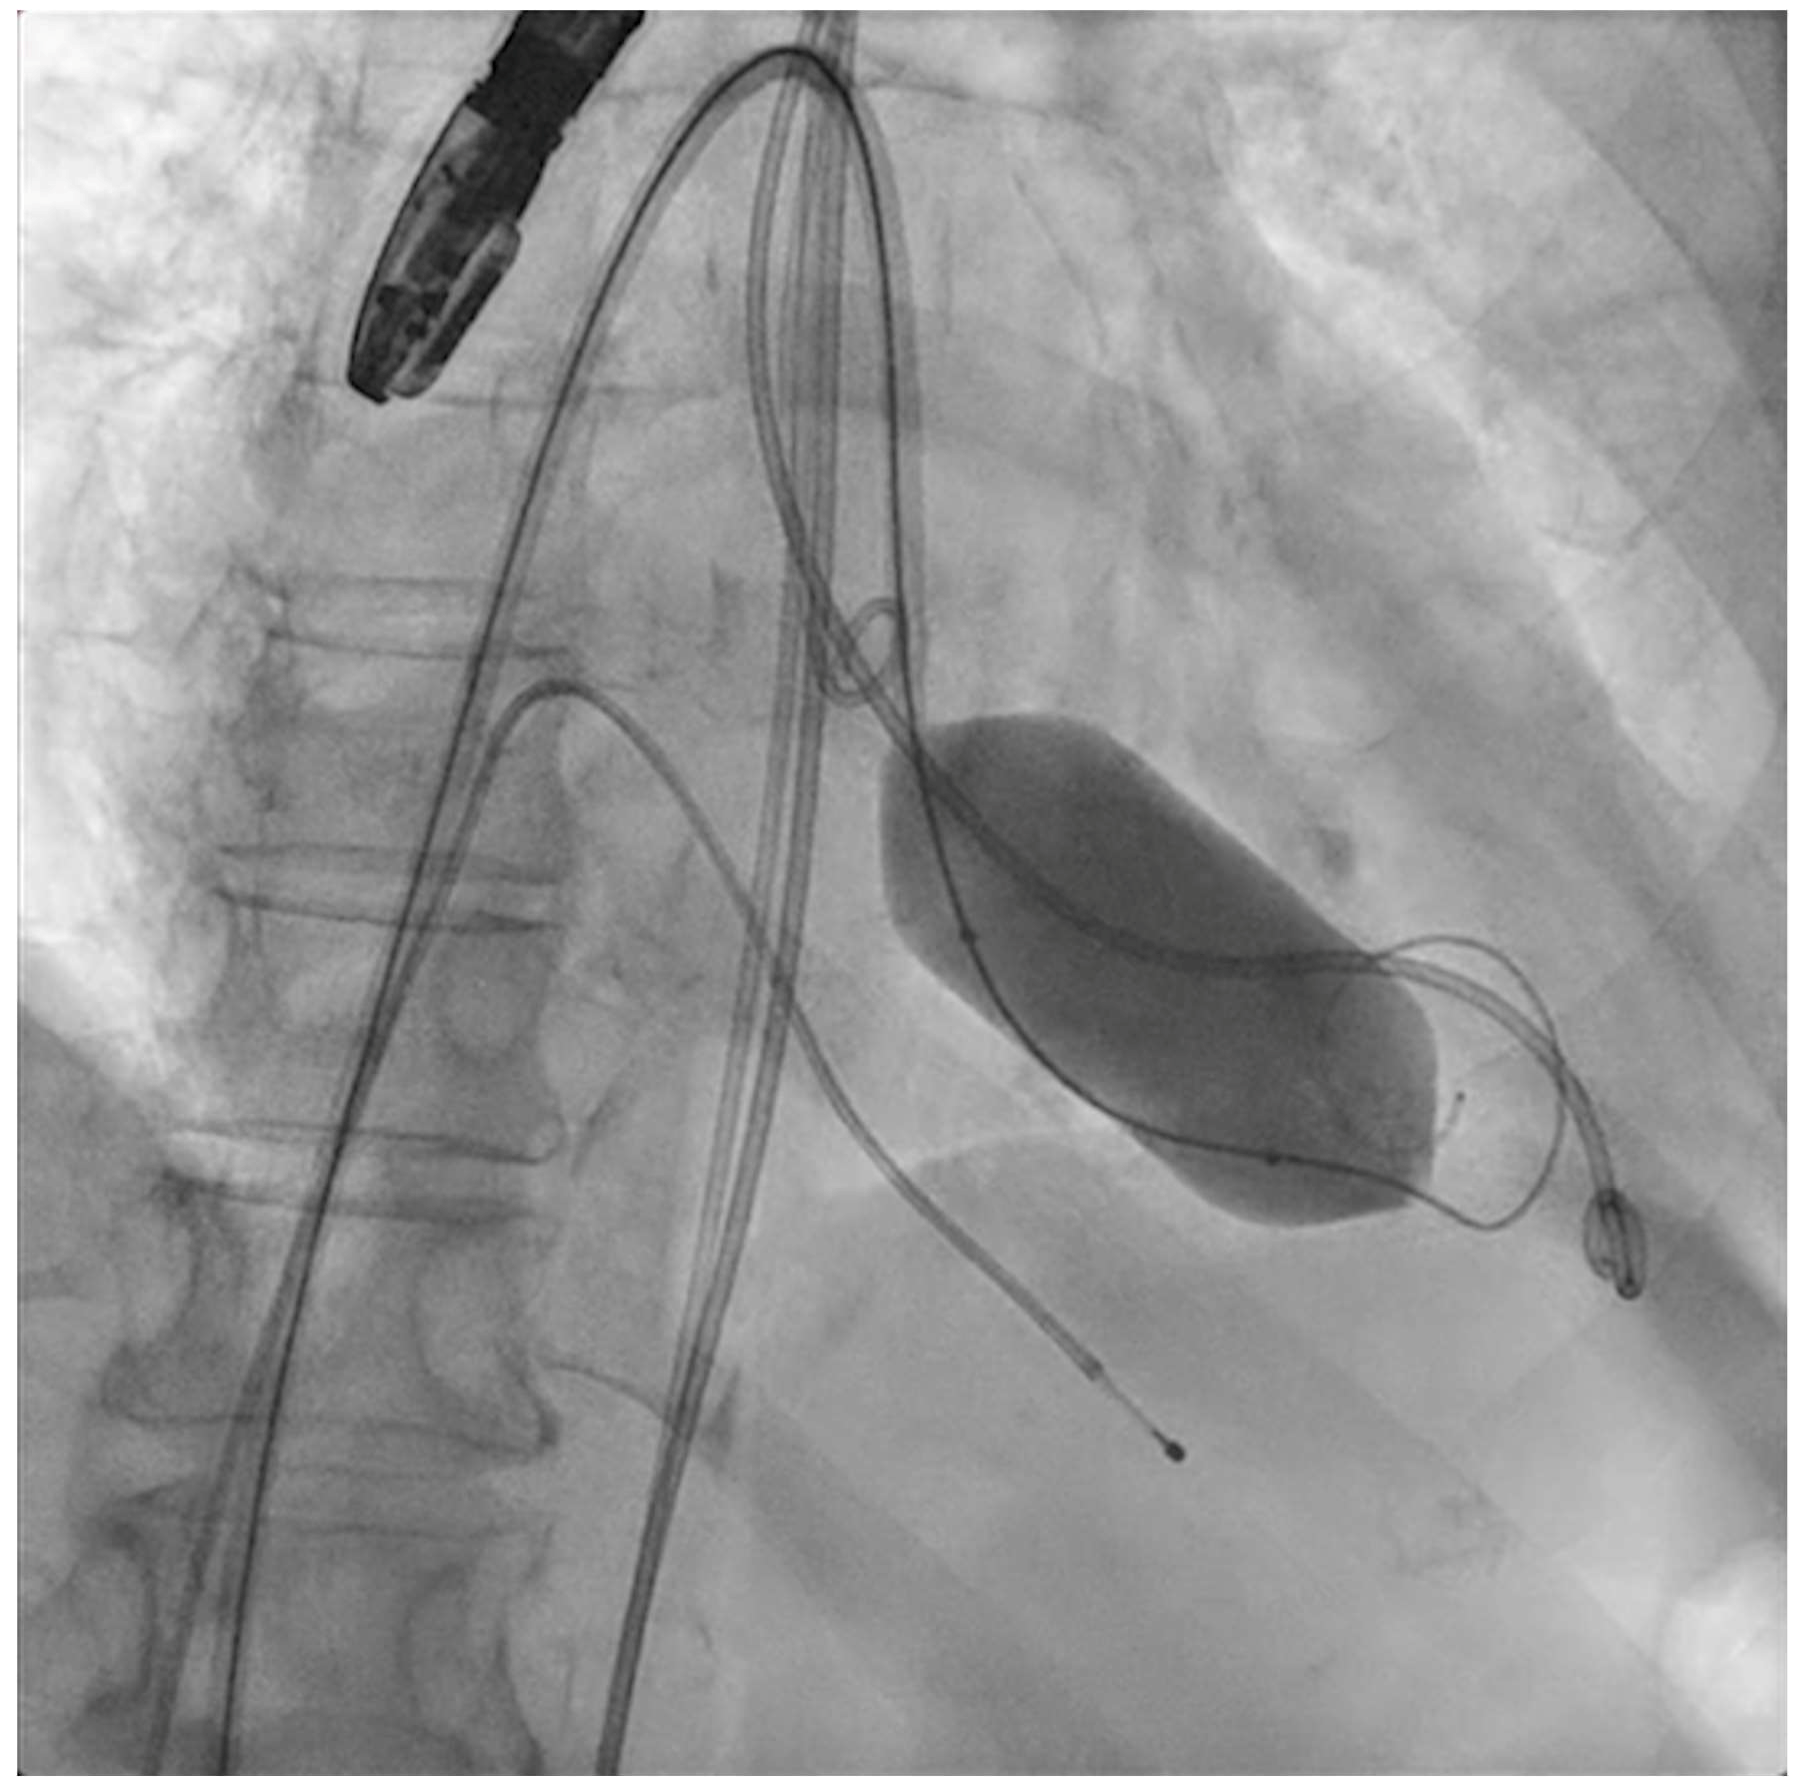

The next steps consist of crossing the mitral valve with three long high-support 0.014´´ wires downstream into the left ventricle (LV) (Figure 2) and then advancing three lithotripsy balloons (Shockwave Medical) across the mitral valve; with rapid pacing (120 beats/min), simultaneous inflations of all balloons will deliver a total of 90 pulses from each balloon (Figure 3). Finally, access to the LV has to be attained again with the Safari wire to complete PMC with large balloons appropriately sized to the mitral valve area and diameters (Figure 4). Embolic protection devices are encouraged to avoid neurological or systemic ischemic events due to calcific debris.

Figure 2.

Three angioplasty wires crossing the mitral valve into the left ventricle.